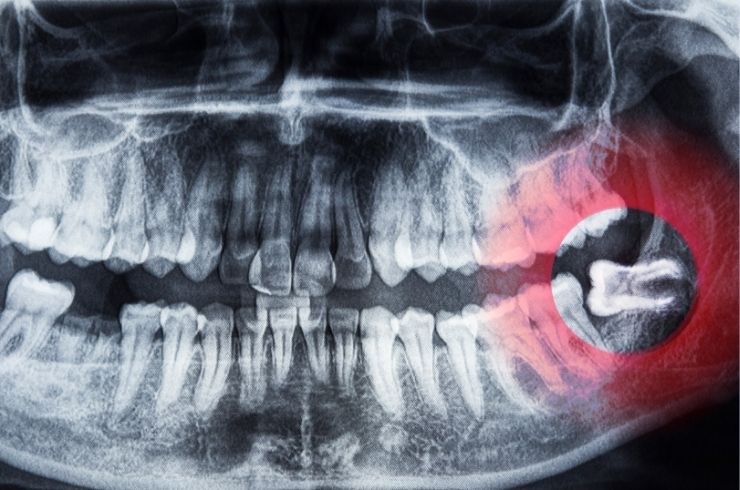

Wisdom tooth removal is a common dental procedure to extract one or more third molars that may be impacted, misaligned, or causing pain. These teeth often do not have enough space to grow properly, leading to swelling, infection, or damage to nearby teeth. At Your Dentist Dental Hospital in Ashok Nagar, Vijayawada, wisdom tooth removal is performed with precision and care to ensure a safe, smooth, and comfortable experience for every patient.

Choosing wisdom tooth removal in Vijayawada helps prevent and relieve multiple dental issues:

Relieves pain, swelling, and discomfort caused by impacted teeth

Prevents infection and damage to surrounding teeth

Reduces risk of cysts and gum complications